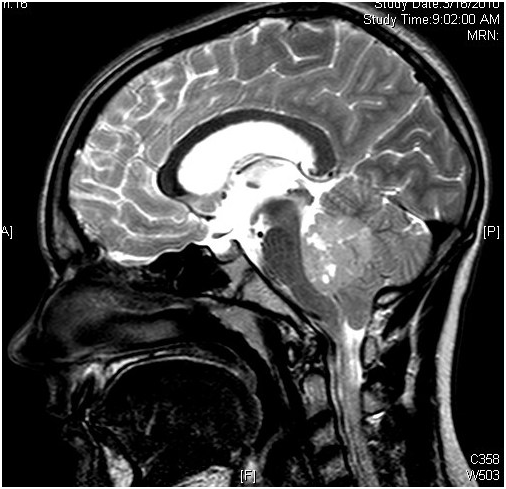

髓母细胞瘤是儿童较常见的恶性脑肿瘤,约占原发性中枢神经系统肿瘤的20%,约占后颅窝肿瘤的40%。它是一种发生于小脑的高级别(WHO IV级)胚胎性神经上皮性肿瘤,有通过脑脊液(CSF)传播的趋势。髓母细胞瘤能活多久?

所以James T. Rutka教授表示,对于髓母细胞瘤,还是主要用手术进行切除,目前国际上在切除髓母细胞瘤时,多采用清醒开颅术。这是一种前沿的手术,也是近年来国际上的新成果,可以在患者清醒时进行手术。清醒开颅术是针对脑功能区病变,以唤醒麻醉、神经电生理监测、神经导航、显微神经外科手术、功能磁共振等多种高要求技术为支撑,术中实时监测手术区域脑功能,较大限度切除脑肿瘤的综合手术技术。